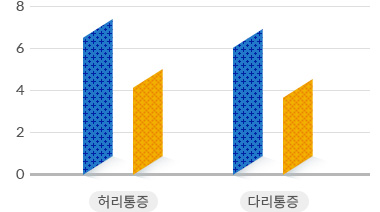

척추관협착증 수술 vs 비수술 치료 통증 감소 효과 비교

수술치료

수술치료

비수술치료

비수술치료